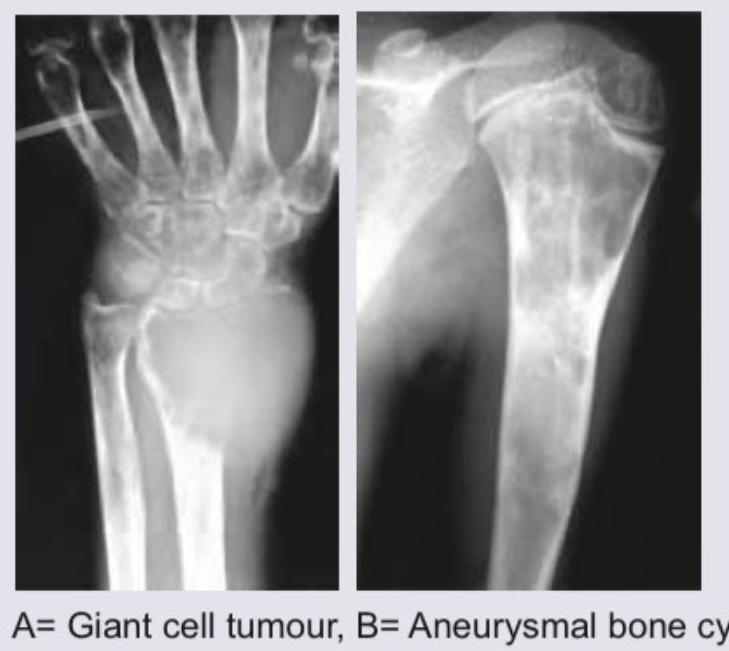

What are the correct diagnoses for lesions A and B shown in the image?

Explanation: ***A= Giant cell tumour, B= Aneurysmal bone cyst*** - Image A shows a **lytic lesion** in the distal radius, extending to the articular surface without sclerotic margins, which is characteristic of a **giant cell tumor (GCT)**. GCTs are typically epiphyseal/metaphyseal and bone-expanding. - Image B shows an **expansile, lytic lesion** in the proximal humerus with internal septations and trabeculations, giving a **"soap bubble" appearance**, classic for an **aneurysmal bone cyst (ABC)**. *A= Simple bone cyst, B= Aneurysmal bone cyst* - A **simple bone cyst (unicameral bone cyst)** is usually centrally located in the metaphysis of long bones, often with a **"fallen fragment sign"** if fractured, and is typically radiolucent and expansile without internal septations. Image A does not show these features. - While Image B is consistent with an aneurysmal bone cyst, Image A is not a simple bone cyst. *A= Aneurysmal bone cyst, B= Simple bone cyst* - As described, Image A is consistent with a **giant cell tumor**, not an aneurysmal bone cyst, due to its characteristic location and aggressive lytic nature near the joint. - Image B shows features of an **aneurysmal bone cyst**, not a simple bone cyst, given its multiseptated appearance. *A= Osteochondroma, B= Aneurysmal bone cyst* - An **osteochondroma** appears as a **bone outgrowth** with a cartilaginous cap, typically arising from the metaphysis and pointing away from the joint. This is clearly not what is seen in Image A. - Image B is consistent with an **aneurysmal bone cyst**, but Image A does not represent an osteochondroma.